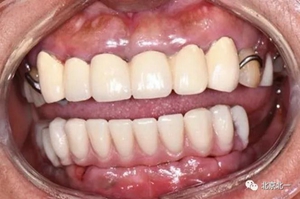

圖二十:永久修復(fù)咬合關(guān)系

圖二十一:半年后復(fù)查X片

圖二十五:口內(nèi)照。